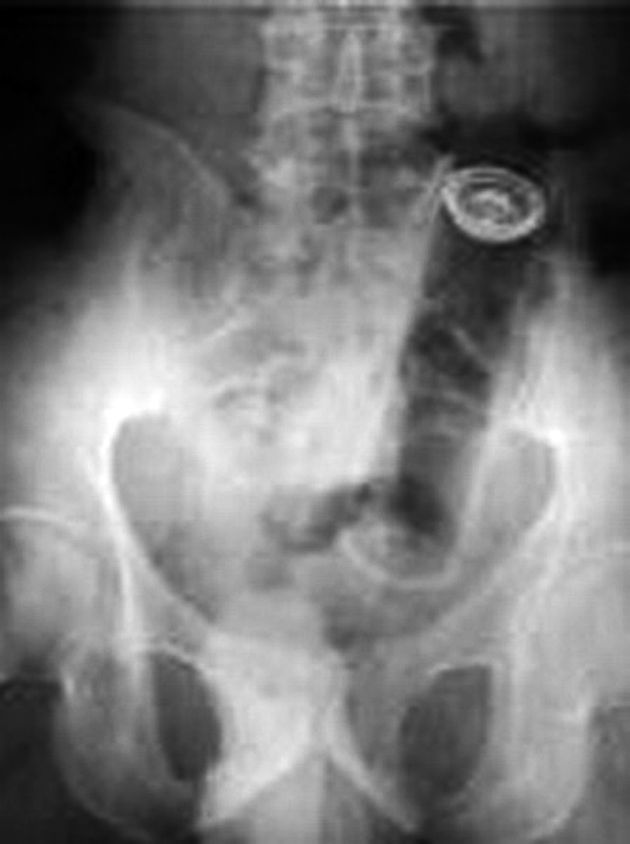

O arădeancă de 37 de ani a ajuns disperată la spital, duminică seara, cerând medicilor să-i scoată un tub de spray care-i rămăsese blocat în… anus.

Managerul Spitalului Clinic Judeţean Arad, Mirandolina Prişcă, a declarat, ieri, că pacienta de 37 de ani s-a prezentat singură la urgenţe, în cursul zilei de duminică, cerând ajutor pentru extragerea tubului de spray.

“S-au făcut radiografii pentru localizarea obiectului, apoi l-am extras, pacienta fiind în stare bună după intervenţie”, a declarat Prişcă.

Managerul spitalului a mai spus că astfel de cazuri sunt foarte rare şi că pacienta nu a vrut să dea explicaţii privind modul în care tubul de spray a ajuns în anusul ei.